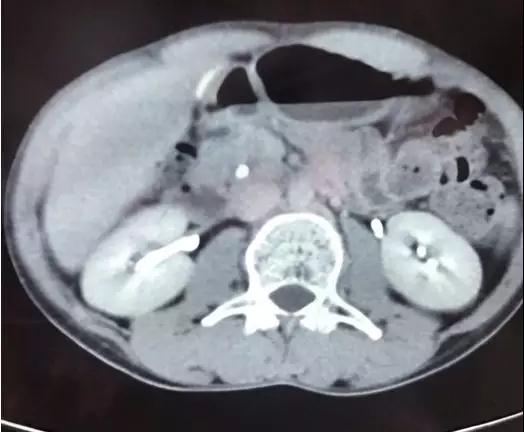

大约一个月前,扎西大夫在群里发了几张CT照片,这是一名反复发作胰腺炎的病人,当地的放射科诊断是“胆总管结石”。由于胆管结石导致的胆源性胰腺炎反复发作,当地大夫考虑第二天为病人做ERCP取石手术。

乍一看,片子上结石的位置好像是在胆管走行区域。但我盯着片子,仔细看过后发现:不是胆管结石,而是胰管结石。在胰头区域,胆管和胰管靠的很近,很容易看走眼。但正所谓“失之毫厘,谬之千里”,如果这个病人真的接受ERCP手术,按照胆管结石处理可就糟了!